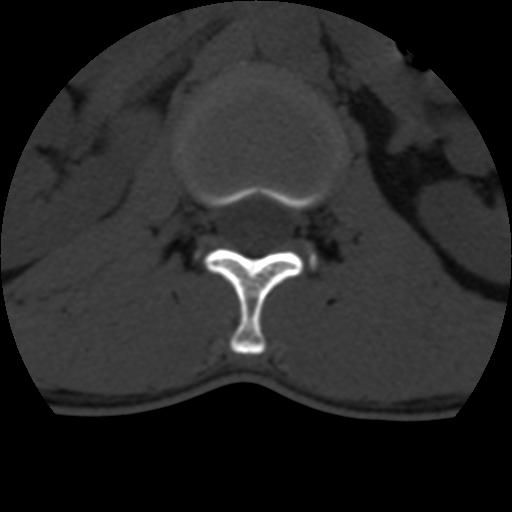

男,31岁,从6米高处坠落伤两天,腰背部疼痛,临床要求ct扫描胸10-腰1。请大家帮忙看看骨质有问题吗?

t12、l1锥体前缘轻度楔形变,平扫示椎体前缘骨小梁欠规整,第9幅图示椎体前缘骨质不连续,结合外伤史考虑椎体轻度压缩骨折。

楼主扫描层厚可能较大,每个椎体只有三个层面.

从所示层面分析,无明确骨折征象,象类似病人我个人会建议mri除外骨挫伤.

从上查骨窗第九片椎体前缘皮质显示断裂.压缩骨折?